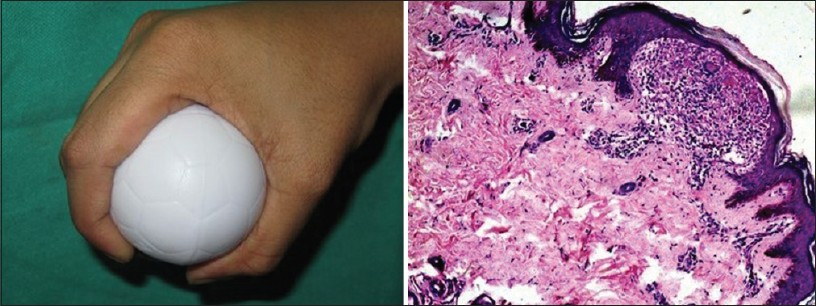

_____ has a characteristic histopathology of "Claw clutching a Ball' appearance